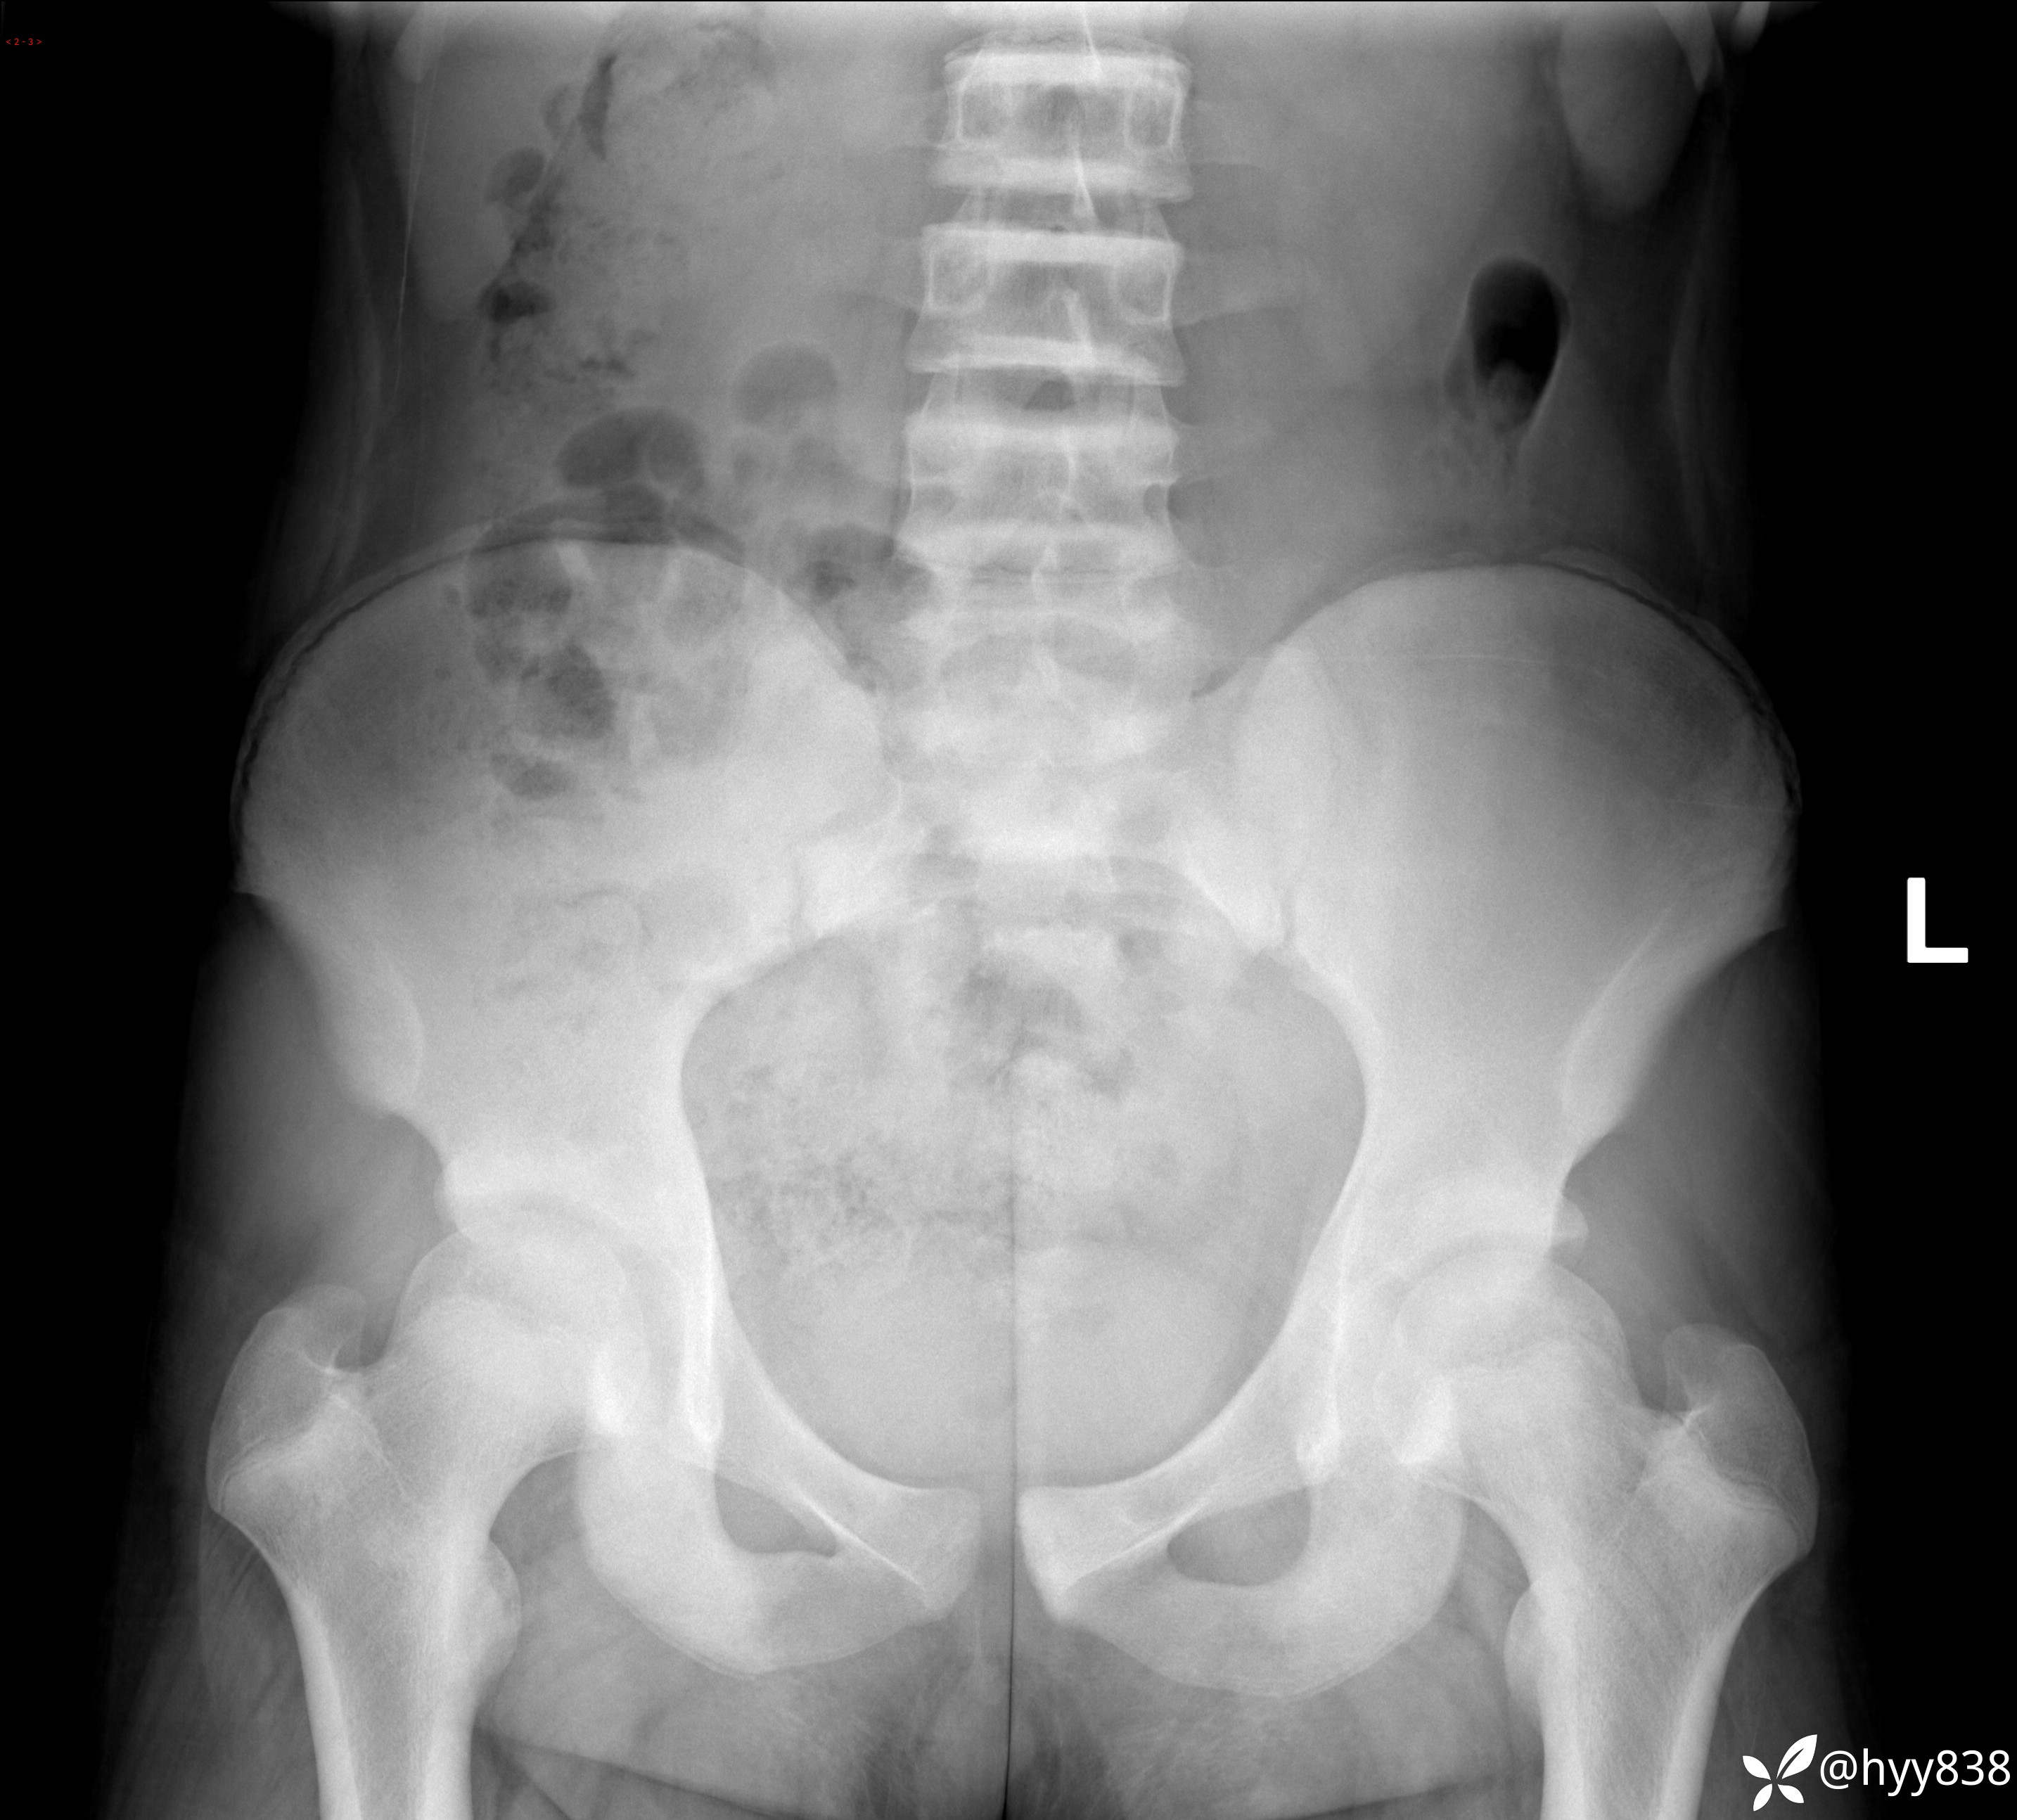

颈椎、胸椎、腰椎正侧位片

img